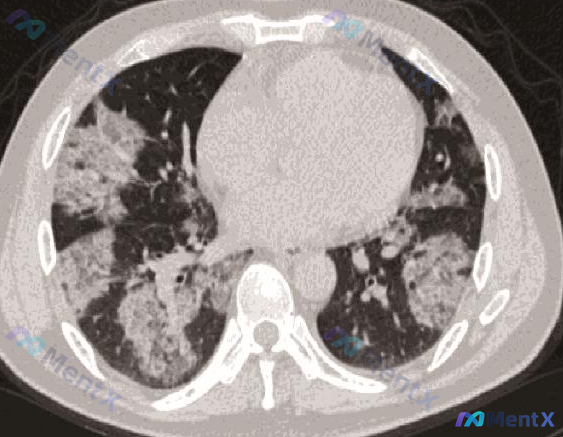

整理到一份胸部CT肺窗横断面的影像分析,先把核心特征放出来,大家第一眼会怎么考虑? 核心影像表现 - 部位:双肺实质,以肺门为中心向中外带延伸,右肺范围更广泛、更致密 - 密度:右肺中下区域大片实变,周边可见磨玻璃影(GGO),有“晕征”样分布;左肺肺门区多发斑片状GGO+实变 - 伴随征象:实变区...